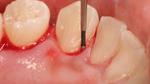

يُعدّ نزيف اللثة من أكثر المشاكل انتشاراً، ويعاني منه الكثير من الناس لأسباب متعدّدة من أبرزها نقص فيتامين (ج)، وتراكم البكتيريا في الفم ويؤدي إلى حدوث التهابات في اللثة ممّا يعمل على إضعافها ويجعلها أكثر عرضة للنزيف، بالإضافة إلى إصابة الأسنان بالتسوّس وانبعاث الروائح الكريهة من الفم، وتآكل الهيكل العظمي للأسنان، ولعلاج نزيف اللثة يجب اتّباع عدّة أمور سنقوم بذكرها.[1]

- إصابة اللثة بالأمراض والالتهابات.